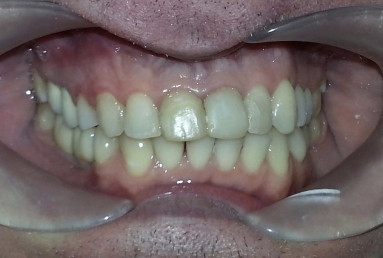

The orthodontic treatment was necessary as the upper maxillary developed assimetricaly, also the teeth were malpositioned. The purpose of the partial braces was to help the final prosthetic treatment, which consisted of two full ceramic crowns for the central incisors, that had root canal treatments, and a ceramic veneer for the lateral incisor, that had a large composite filling. Gingivectomies were also necessary for the right canine and incisors in order to correct the assymetrical gummy smile.